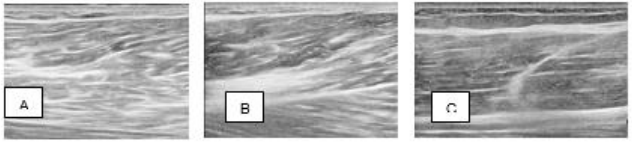

A 73-year-old male tennis player presented with an acute pain in the left posterior thigh while playing tennis. He stated he had a heavy total body exercise training program the day prior and after an extensive dynamic warmup prior to playing tennis the day of injury. While planting the left foot and eccentrically loading his hamstring muscles to make a shot, he experienced a sudden sharp pain in the posterior mid-thigh and was unable to continue playing. He had difficulty walking and extending his knee. He reported no prior injuries to the left lower extremity in the past. Physical exam revealed tenderness over the mid biceps femoris muscle belly with a small painful palpable defect in the muscle. Diagnostic ultrasound evaluation revealed a hematoma at the side of injury within the muscle belly and disruption of the normal muscle morphology (Figure 1). A decision was made to treat the muscle injury with a cell-based therapy using autologous PRM under ultrasound guidance (Tables 1 and 2). The same post procedure instructions were recommended to this patient as with case 1. The patient presented for a reevaluation 1 week post procedure with no post-procedural pain VAS 0/10. He continued to limit knee flexion and extension to minimize stress and load across the biceps femoris muscle treatment site. At the beginning of the third week post treatment, the patient was started on a formal goal-based muscle specific rehabilitation exercise program (Table 3). At 4 weeks post procedure, he was reevaluated and at his own discretion, decided to go snow skiing. He reported to be able to ski without any pain or restrictions and exhibited normal strength during his physical exam. At 8 weeks post procedure, he was reevaluated having no pain in his left hamstring muscle. He began a progressive return to play tennis. A diagnostic musculoskeletal ultrasound Figure 1 Case 1: Ultrasound images of the right rectus femoris muscle partial tear injury, A. Pretreatment; B. and C. Time of treatment; D. 24 weeks post-treatment. of the left hamstring was performed with evidence of a healed biceps femoris muscle (Figure 2).

Figure 2 Case 2: Ultrasound images of the right biceps femoris muscle partial tear injury, A. and B. Pretreatment; C. 24 weeks post-treatment.